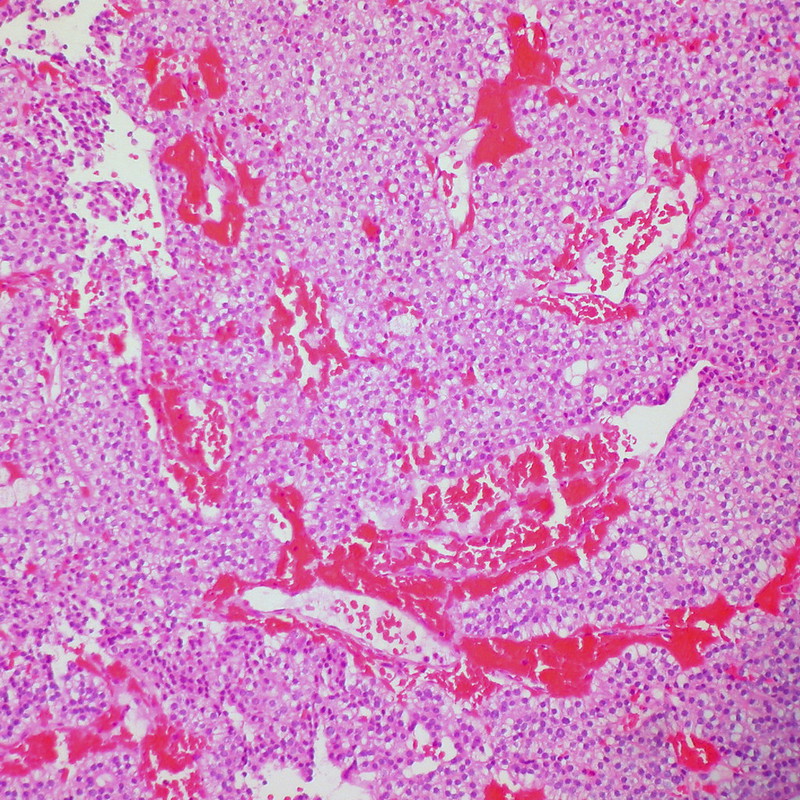

Hepatocellular Carcinoma (HCC)

Hepatocellular carcinoma (HCC) is the malignant tumor of hepatocytes, in contrast to hepatic adenoma.

Risk factors for hepatocellular carcinoma (HCC) include:

Hepatocellular carcinoma (HCC) presents with severe hepatomegaly and ascites.

The prognosis of hepatocellular carcinoma (HCC) is poor.

Hepatocellular carcinoma (HCC) produces the serum tumor marker alpha-fetoprotein (AFP).